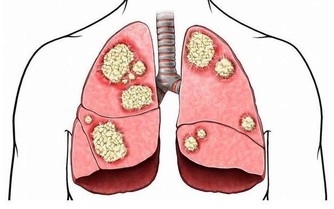

化療藥:幾乎所有的化療藥都可能損害腎臟。

值得注意的是,中草藥引起的腎損傷約佔所有藥物性腎損傷的60%。這些中草藥主要是含有馬兜鈴酸的藥物包括:關木通、廣(粉)防己、青木香、馬兜鈴等。常見的成藥包括:龍膽瀉肝丸、甘露消毒丸、婦科分清丸、分清五淋丸、冠心蘇合丸等。中草藥引起的腎損傷除了損傷腎小管之外,還導致腎間質的病變。